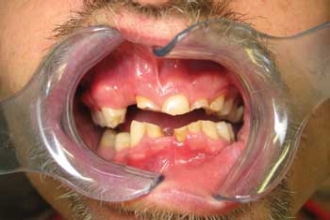

He ordered both upper and lower Snap-On Smile arches, then took care of his payment and made his delivery appointment. I can tell you that the delivery was one unforgettable appointment for my staff, my patient, and me.

As soon as we placed his new Snap-On Smile, his entire demeanor changed. He not only looked like a different man, I felt like he was taking a new direction in his life. Just one look at his face and we saw the most powerful testimonial I could imagine. Don't tell anyone, but even I felt tears in my eyes.

And if, in the future, Happy wants a permanent smile, I can match his new crowns to his Snap-on Smile. His teeth can be restored sequentially by using Snap-On Smile as a temporary while he saves up for each phase of treatment.

As I write this, I can tell you that Happy has been going on job interviews and is actively looking for a girlfriend. His confidence has skyrocketed and he has a totally new respect for himself and the way he looks. His future is as bright as his smile. I know that he can finally live up to his name, and there's nothing better than that. Snap-On Smile is a versatile, affordable, and potentially life-changing treatment option for patients, one that I'm glad we're able to offer.